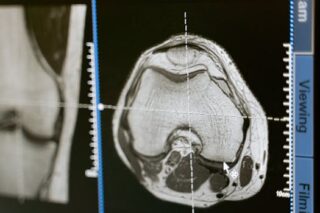

An MRI, or magnetic resonance imaging, of the lumbar spine without contrast is a medical imaging procedure used to visualize the lower part of the spine. It uses magnetic fields and radio waves to create detailed images of the lumbar region without the use of a contrast agent. This type of MRI is commonly used to diagnose conditions like herniated discs, spinal stenosis, and degenerative disc disease.

The MRI machine is a large, tube-like structure. You’ll be asked to lie still on a movable table, which slides inside the magnet. The procedure is painless, but it can be noisy, so technicians often provide earplugs or headphones. Although the entire process takes about 45 minutes to an hour, staff will communicate with you through an intercom to ensure your comfort.